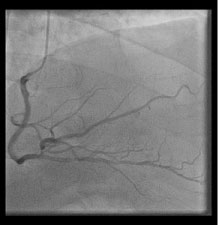

Figure 4: The right coronary artery is super dominate and expands to supply blood flow to the lateral wall that would be supplied by the absent left circumflex artery in this right anterior oblique, cranial view via cinematography during the left heart catheterization. View Figure 4

Congenital anomalies of the coronary vasculature are usually asymptomatic and rare with an incidence of less than 1% [1]. Complete absence of the left circumflex is an extremely rare finding with reported incidence of only 0.003% [2]. There are few cases reported of congenital absence of the left circumflex artery but in each case there is an elongated left main coronary artery (Figure 1), substantial diagonal branches from the left anterior descending artery (Figure 2 and Figure 3), and a super-dominate right coronary artery (Figure 4) to perfuse the lateral wall. It is important to recognize this anomaly and define the anatomy by left heart catheterization or coronary angiography by computerized tomography when considering percutaneous intervention or coronary artery bypass surgery on patients without a left circumflex artery [3].